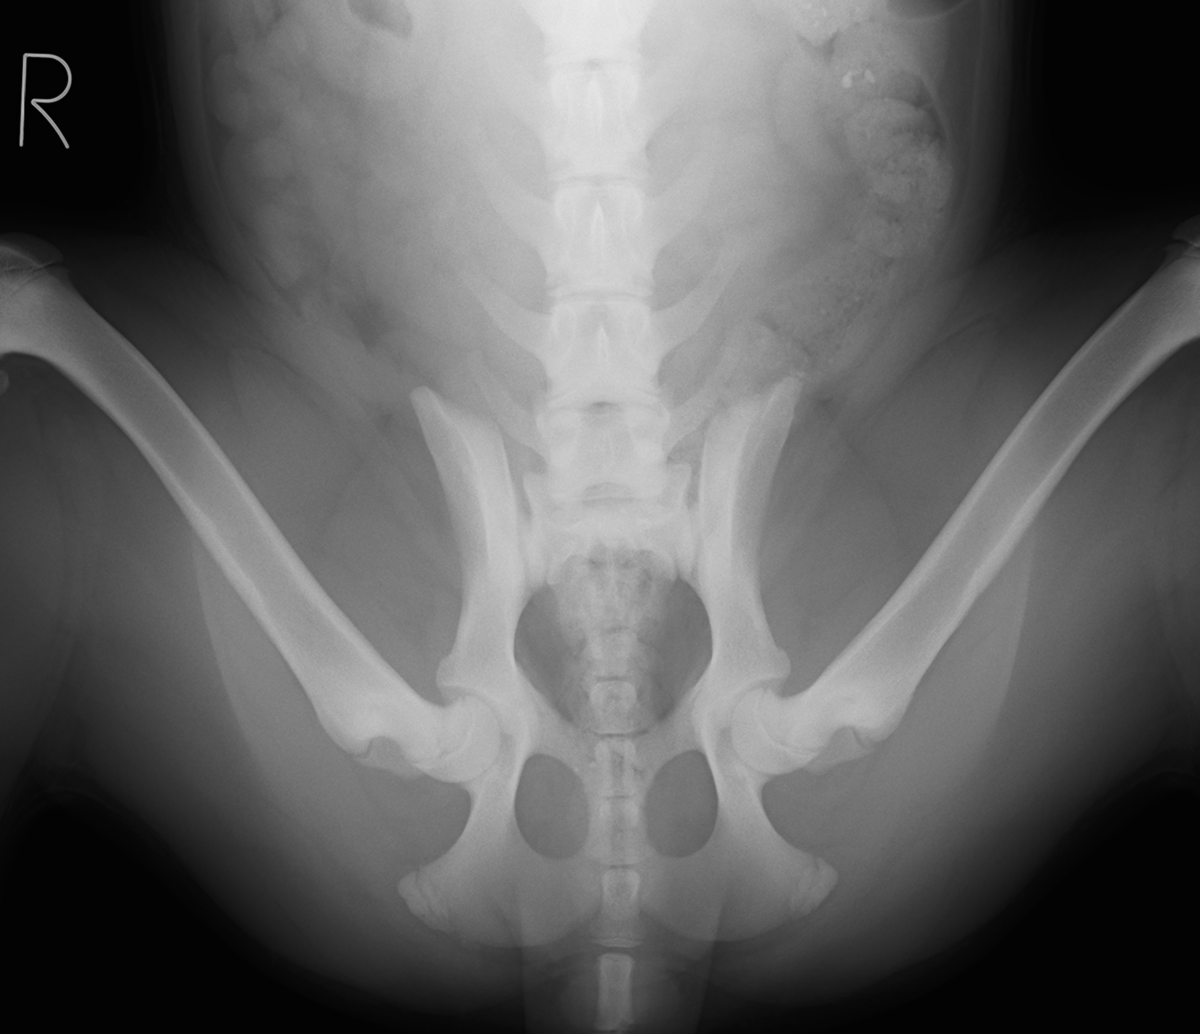

病院犬(生後約4ヶ月)の股関節を、PennHIP(ペンヒップ)という特殊器具を用いたレントゲン撮影を先日実施しました。

撮影をした理由としては少し腰を振って歩いていたり、足を投げ出す様に座っていていて、股関節形成不全が疑われたからです。

下にあるのが実際に撮影したレントゲンになります。

下の図にあるようなディストラクター(下の写真)とよばれる特殊な器具を用いて、三つの体位で股関節を撮影し、股関節の緩みをレントゲン画像上で可視化し、その緩みの数値を測定します。